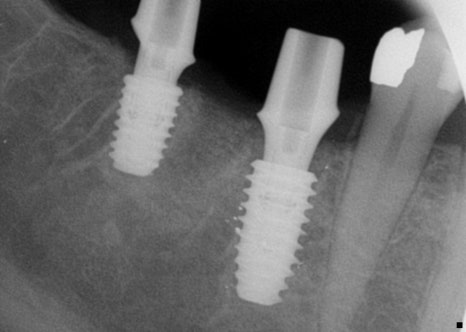

또한 치근단 촬영을 진행해 치아 전체적으로

주변 뼈를 자세히 촬영하여

여러 상태 확인을 합니다.

픽스쳐의 위치, 골유착여부, 보철물 체결 상태,

피개나 파절 여부를 확인했습니다.